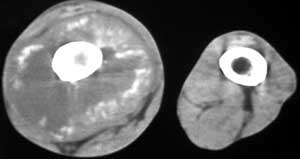

男56涨疼5-6月

右股骨下端包绕股骨见巨大软组织肿块,密度部俊,周围见瘤骨,下端骨皮质侵蚀变薄,骨质周围无骨膜反应, 考虑右股骨软骨肉瘤。

右股骨下段周围软组织肿块伴钙化,相邻股骨骨皮质受累,考虑软组织来源恶性病变

右股骨下段骨肉瘤,软组织内瘤骨,软组织肿块。